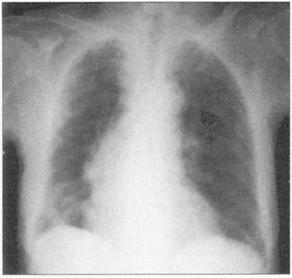

图81 大叶性肺炎,这个患者有右肺实变

图82 单纯疱疹病毒感染在大叶性肺炎患者常见